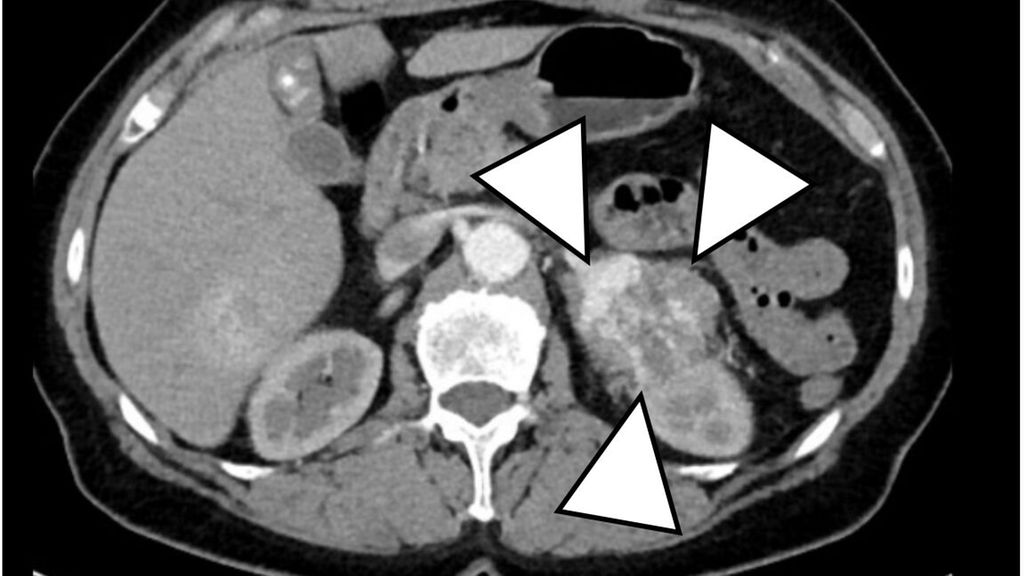

Nach Bestätigung der CS-Diagnose erfolgen weitere Tests zur Lokalisationsdiagnostik. Bei massiver Hypercortisolämie wird umgehend eine Computertomografie von Thorax und Abdomen empfohlen (Abb. 1). Plasma-ACTH-Konzentrationen helfen zur biochemischen Differenzialdiagnose zwischen ACTH-abhängigem und -unabhängigem CS. Für die Lokalisationsdiagnostik des ACTH-abhängigen CS werden ein CRH-Test, ein Langzeit-Dexamethason-Hemmtest sowie eine Hypophysen-MRT benötigt (Abb. 2). Ein Hypophysenadenom ist als Zufallsbefund bei bis zu 10% der Bevölkerung zu erwarten, andererseits lässt sich nur bei 60% der Patienten mit hypophysärem CS ein Hypophysenadenom lokalisieren. In unklaren Fällen wird eine Sinus-petrosus-inferior-Katheterisierung für die Lokalisationsdiagnostik benötigt.5

Abb. 1:CT Abdomen mit Nebennierenkarzinom (>5 cm) links